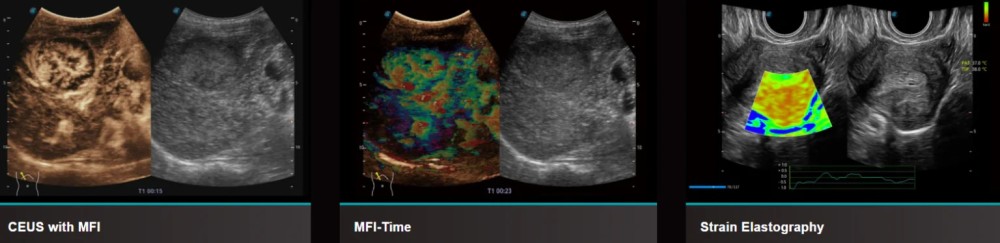

- CEUS ilə MFI və MFI-Time (kontrast / perfuziya)

- Elastoqrafiya (konveks, linear, endokavyum prob ilə)